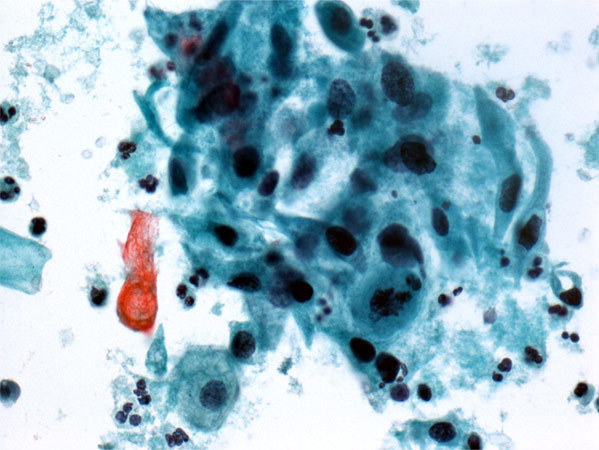

SCC on Pap